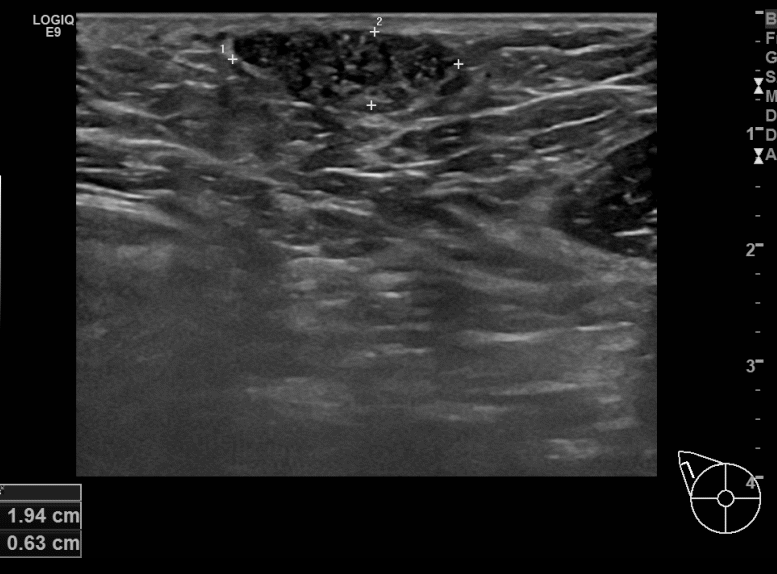

아산유외과개원후 693번째 유방암진단

상기환자 본원에서 정기검진하시던 40대 여성분으로 우측겨드랑이에에 딱딱한 멍울생겨 조직검사시행후 유방암 진단되었습니다